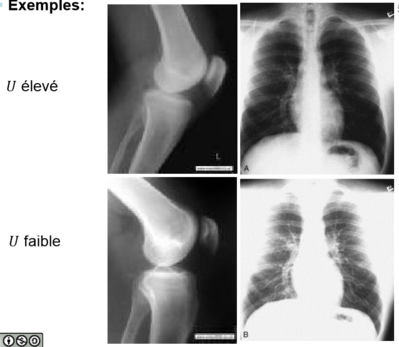

-B) C'est bien vrai. Pourquoi? Parce que lorsque que tu envoie une tension faible c'est l'effet photo-électrique qui est privilégié et qui est Z dépendant! Les os ont un numéro atomique assez élevé par rapport au tissu mou (Ca=20 et tissu mou c'est de l'eau) donc on verra un meilleur contraste. Je te mets une ptite photo:

Tu vois bien qu'un U faible est adapté pour l'os (en l'occurrence au niveau du fémur, tibia, fibula) et un U fort est adapté pour les tissus mou (ici les poumons) :wink2: